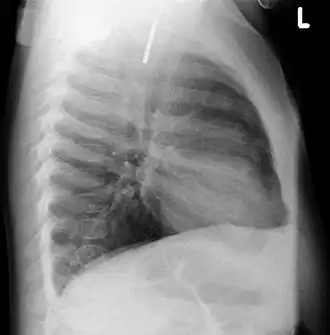

A coin seen on AP CXR in the esophagus -

A coin seen on lateral CXR in the esophagus -